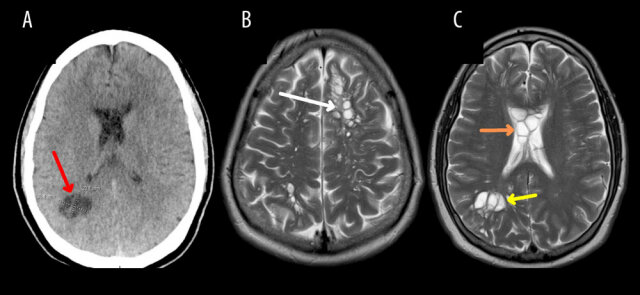

КТ показала множественные кисты в белом веществе мозга, а проведенная уже в больнице МРТ выявила еще больше кист в твердой оболочке мозга, а также отек.